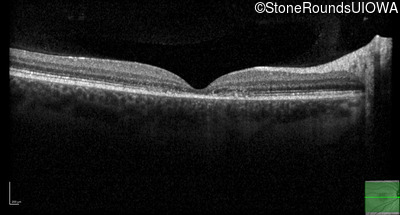

AR Stargardt Disease (IIA)

Age at visit: 20 years

Age at visit: 22 years

This 20 year old man first noticed some difficulty reading the board at school in 9th grade 20 in 2017